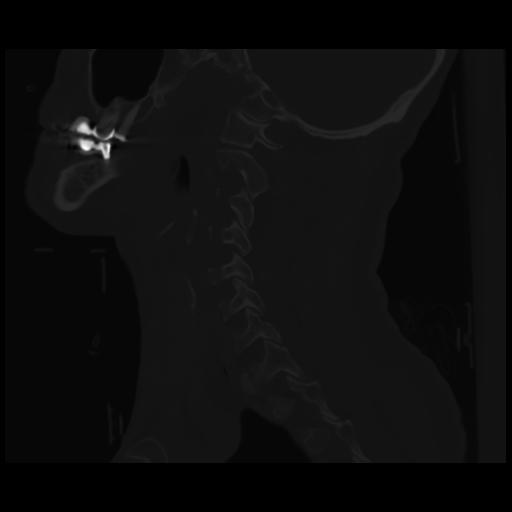

14 P.BLANDAS,,Sagittal,2.000,P.BLANDAS,Sagittal,